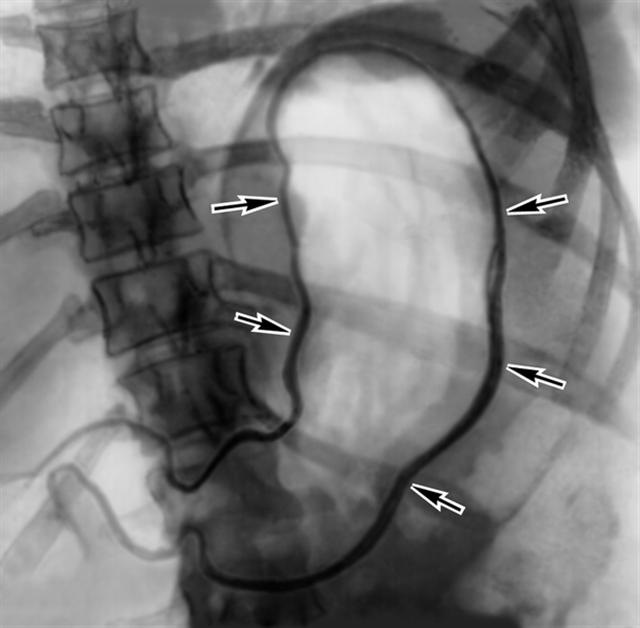

Рис. а). Париетограмма желудка в норме: толщина стенки желудка (указана стрелками) не превышает 2 мм.